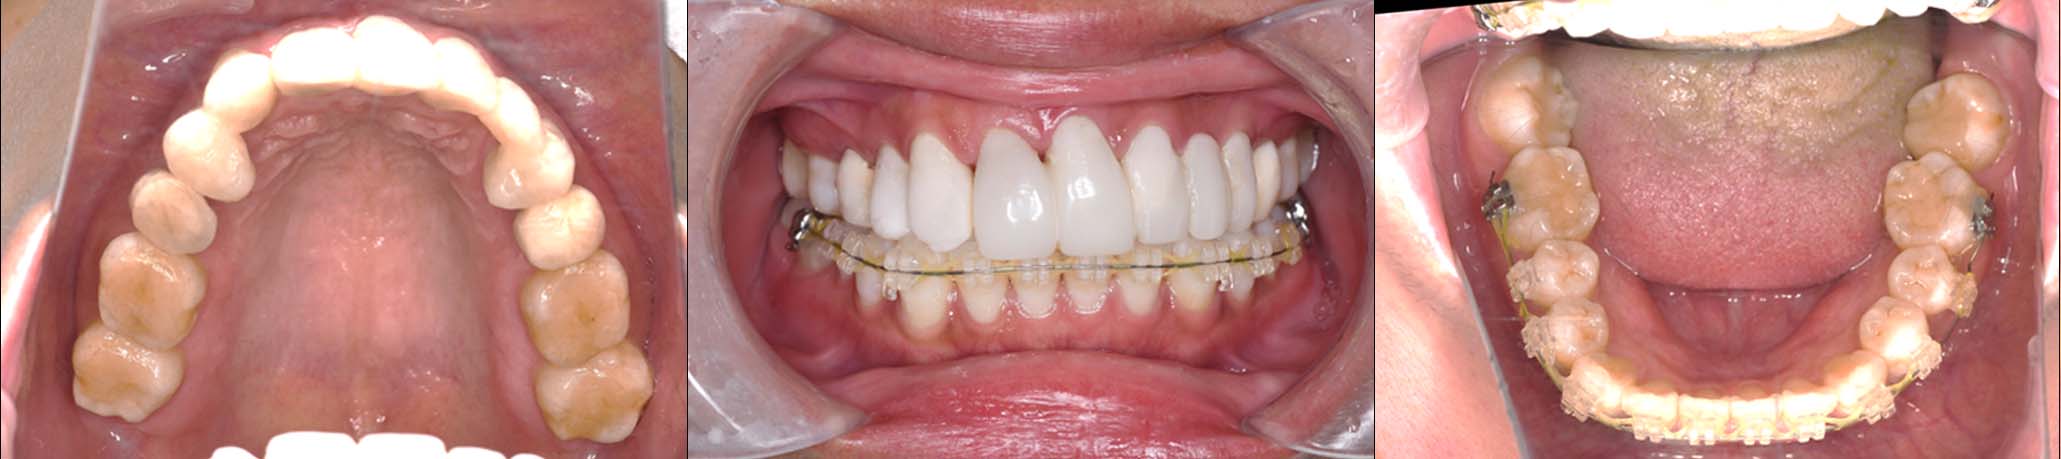

2024年 10月 下顎MTM開始

2024年 10月10日